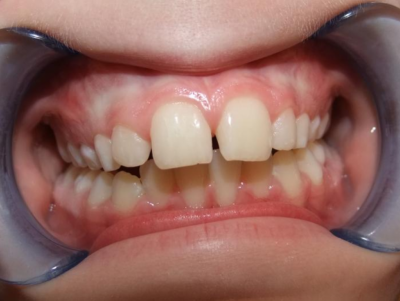

eindfoto

Beschrijving

Leeftijd bij aanvang: 9 jaar

1-6 Bonded Hyrax + volledig vast onderkaak & TransForce

7-13 Twin Block

14-26 volledig vast boven- en onderkaak + TPA

Leeftijd bij retentie: 11 jaar